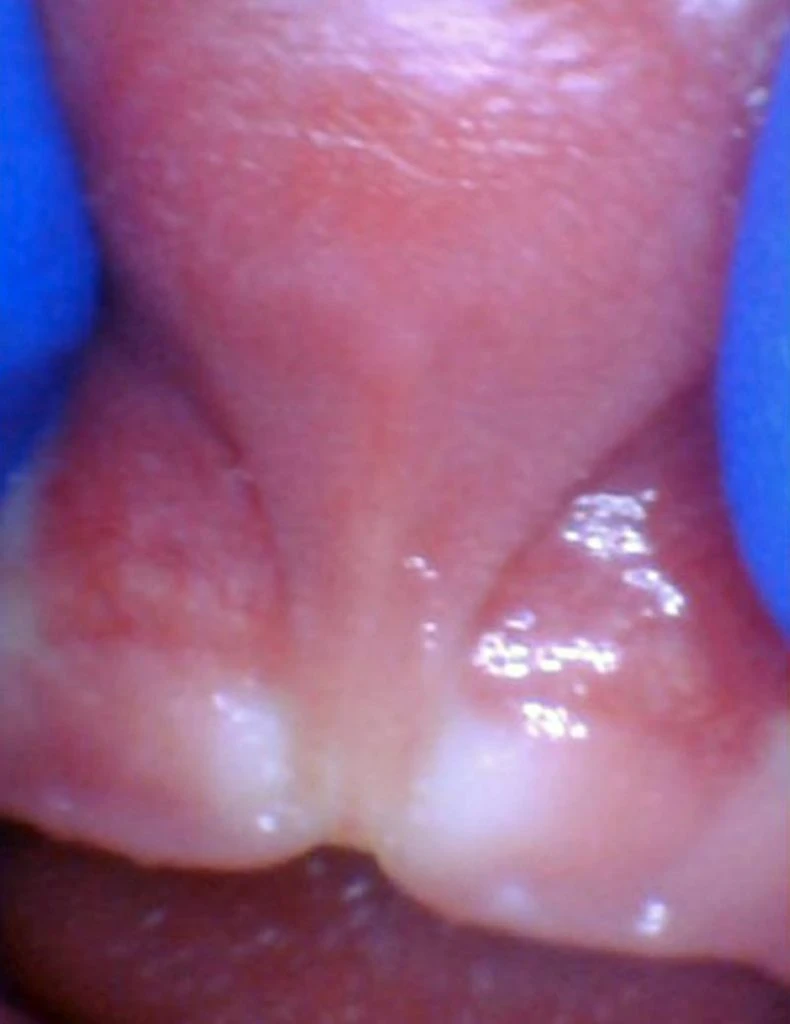

These images show the spectrum of posterior tongue restriction in an infant.

View posterior tongue restrictions

These images show the spectrum of posterior tongue restriction in a child.